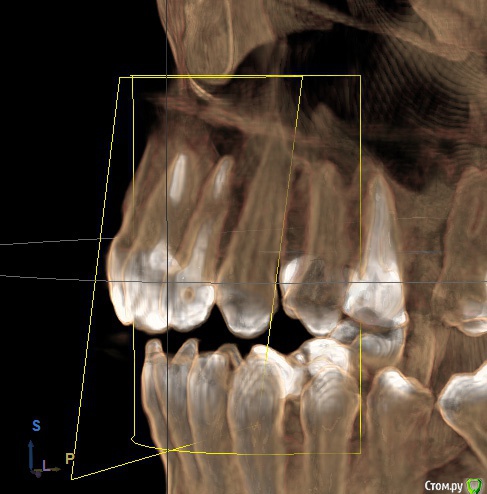

Ankazabolevshaya Опубликовано 28 мая, 2016 Поделиться Опубликовано 28 мая, 2016 Здравствуйте, уважаемые врачи! Очень сильно нуждаюсь в вашей помощи. В 2013 мне лечили два передних зуба (клык и передний). Пломбировали каналы, но коронки не ставили. Этой зимой я почувствовала боль в передних зубах в районе челюсти. Раздражение в дёснах. Резь. Потом вылез какой-то пупырь на десне. Я думала, что это стоматит. Не верила тем, кто мне говорил про нужность обзорного снимка. Признаю свою глупость. Теперь, после КТ оказалось что у меня сломаны эти каналы, а под левым клыком пустота. А пупырь, как мне сказали - это выход свища.Мне предложили зуб удалять. Как-то восстанавливать эту пустоту. Потом делать имплантацию. Есть ли сегодня технологии, позволяющие восстанавливать это пространство под зубом без его удаления, с последующей коронкой на него? И ещё один вопрос: могло ли все это случится из-за какой-нибудь заразы, занесенной во время лечения этих двух зубов в 2013г. ? Так же был момент ранения слизистой левой ноздри, как раз над свищем, который на десне. Просто очень часто слизистая иссыхала в одном месте и я травмировала слизистую. Буду очень благодарна за ответ. От меня в клинике ждут решения, а я переживаю, что улыбка испортится с искусственным зубом. Зуб этот свой очень люблю. Анна. Ссылка на комментарий

red_butler Опубликовано 28 мая, 2016 Поделиться Опубликовано 28 мая, 2016 Спасибо! Можете пояснить, Вы думаете, что зуб можно спасти? если судить только по снимкам, то да 1 Ссылка на комментарий

red_butler Опубликовано 29 мая, 2016 Поделиться Опубликовано 29 мая, 2016 а скажите, как по Вашему, это киста прикорневая? Или челюсть разрушена? Нужно восстановление челюсти? это не важно и корень ведь сломан, поставить под коронки всё равно можно? перелома не увидел И еще последнее, как Вы относитесь к процедуре - депофорез? В моём случае стоит в эту торону смотреть? бесполезно 2 Ссылка на комментарий